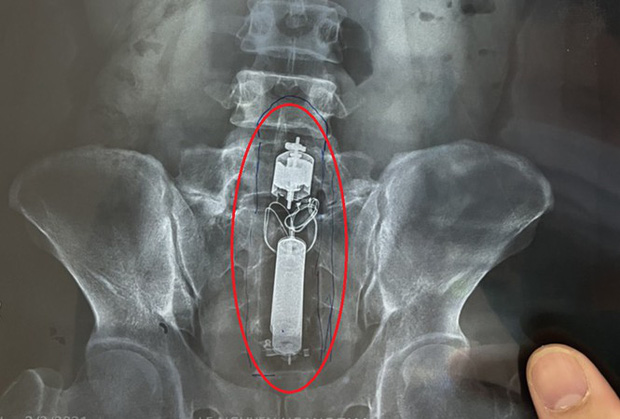

04/02/2021 23:21Nam thanh niên cấp cứu do kẹt dương vật giả trong trực tràng

Ngày 4/2, bác sĩ Trần Hà Hiếu, Chủ nhiệm khoa Nội tiêu hóa, Bệnh viện Quân y 175 cho biết, đơn vị vừa thực hiện lấy ra dụng cụ tình dục (sextoy) là dương vật giả trong trực tràng nam thanh niên (31 tuổi, ngụ TPHCM).

Theo đó, nam thanh niên dùng sextoy ở nhà nhưng không may bị mắc kẹt trong trực tràng nên phải đi bệnh viện. Sau khi tiếp nhận bệnh nhân, các bác sĩ Bệnh viện Quân y 175 tiến hành cấp cứu và chuyển vào phòng mổ.

Qua kiểm tra, các bác sĩ xác định sextoy lớn kẹt trong trực tràng bệnh nhân. Các bác sĩ quyết định không phẫu thuật mà cố gắng lấy dị vật bằng kỹ thuật nội soi. Tuy nhiên, do không có dụng cụ y tế chuyên dụng để lấy nên các bác sĩ mất gần 3 giờ vẫn không lấy ra được. Sau đó, bác sĩ tiến hành thụt tháo thì sextoy trôi xuống và được lấy ra thành công. Bệnh nhân đã xuất viện sau đó.

Các bác sĩ cho biết, có nhiều trường hợp bệnh nhân bị dị vật bị trôi vào trực tràng và phải mổ lấy ra do dị vật là loại khó lấy bằng nội soi. Tuy nhiên, nếu phải phẫu thuật lấy dị vật thì bệnh nhân phải làm hậu môn nhân tạo, ca mổ phức tạp hơn.